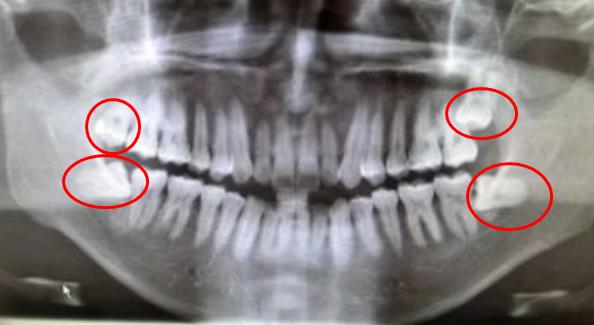

全景片中,紅圈內(nei) 的就是4顆智齒